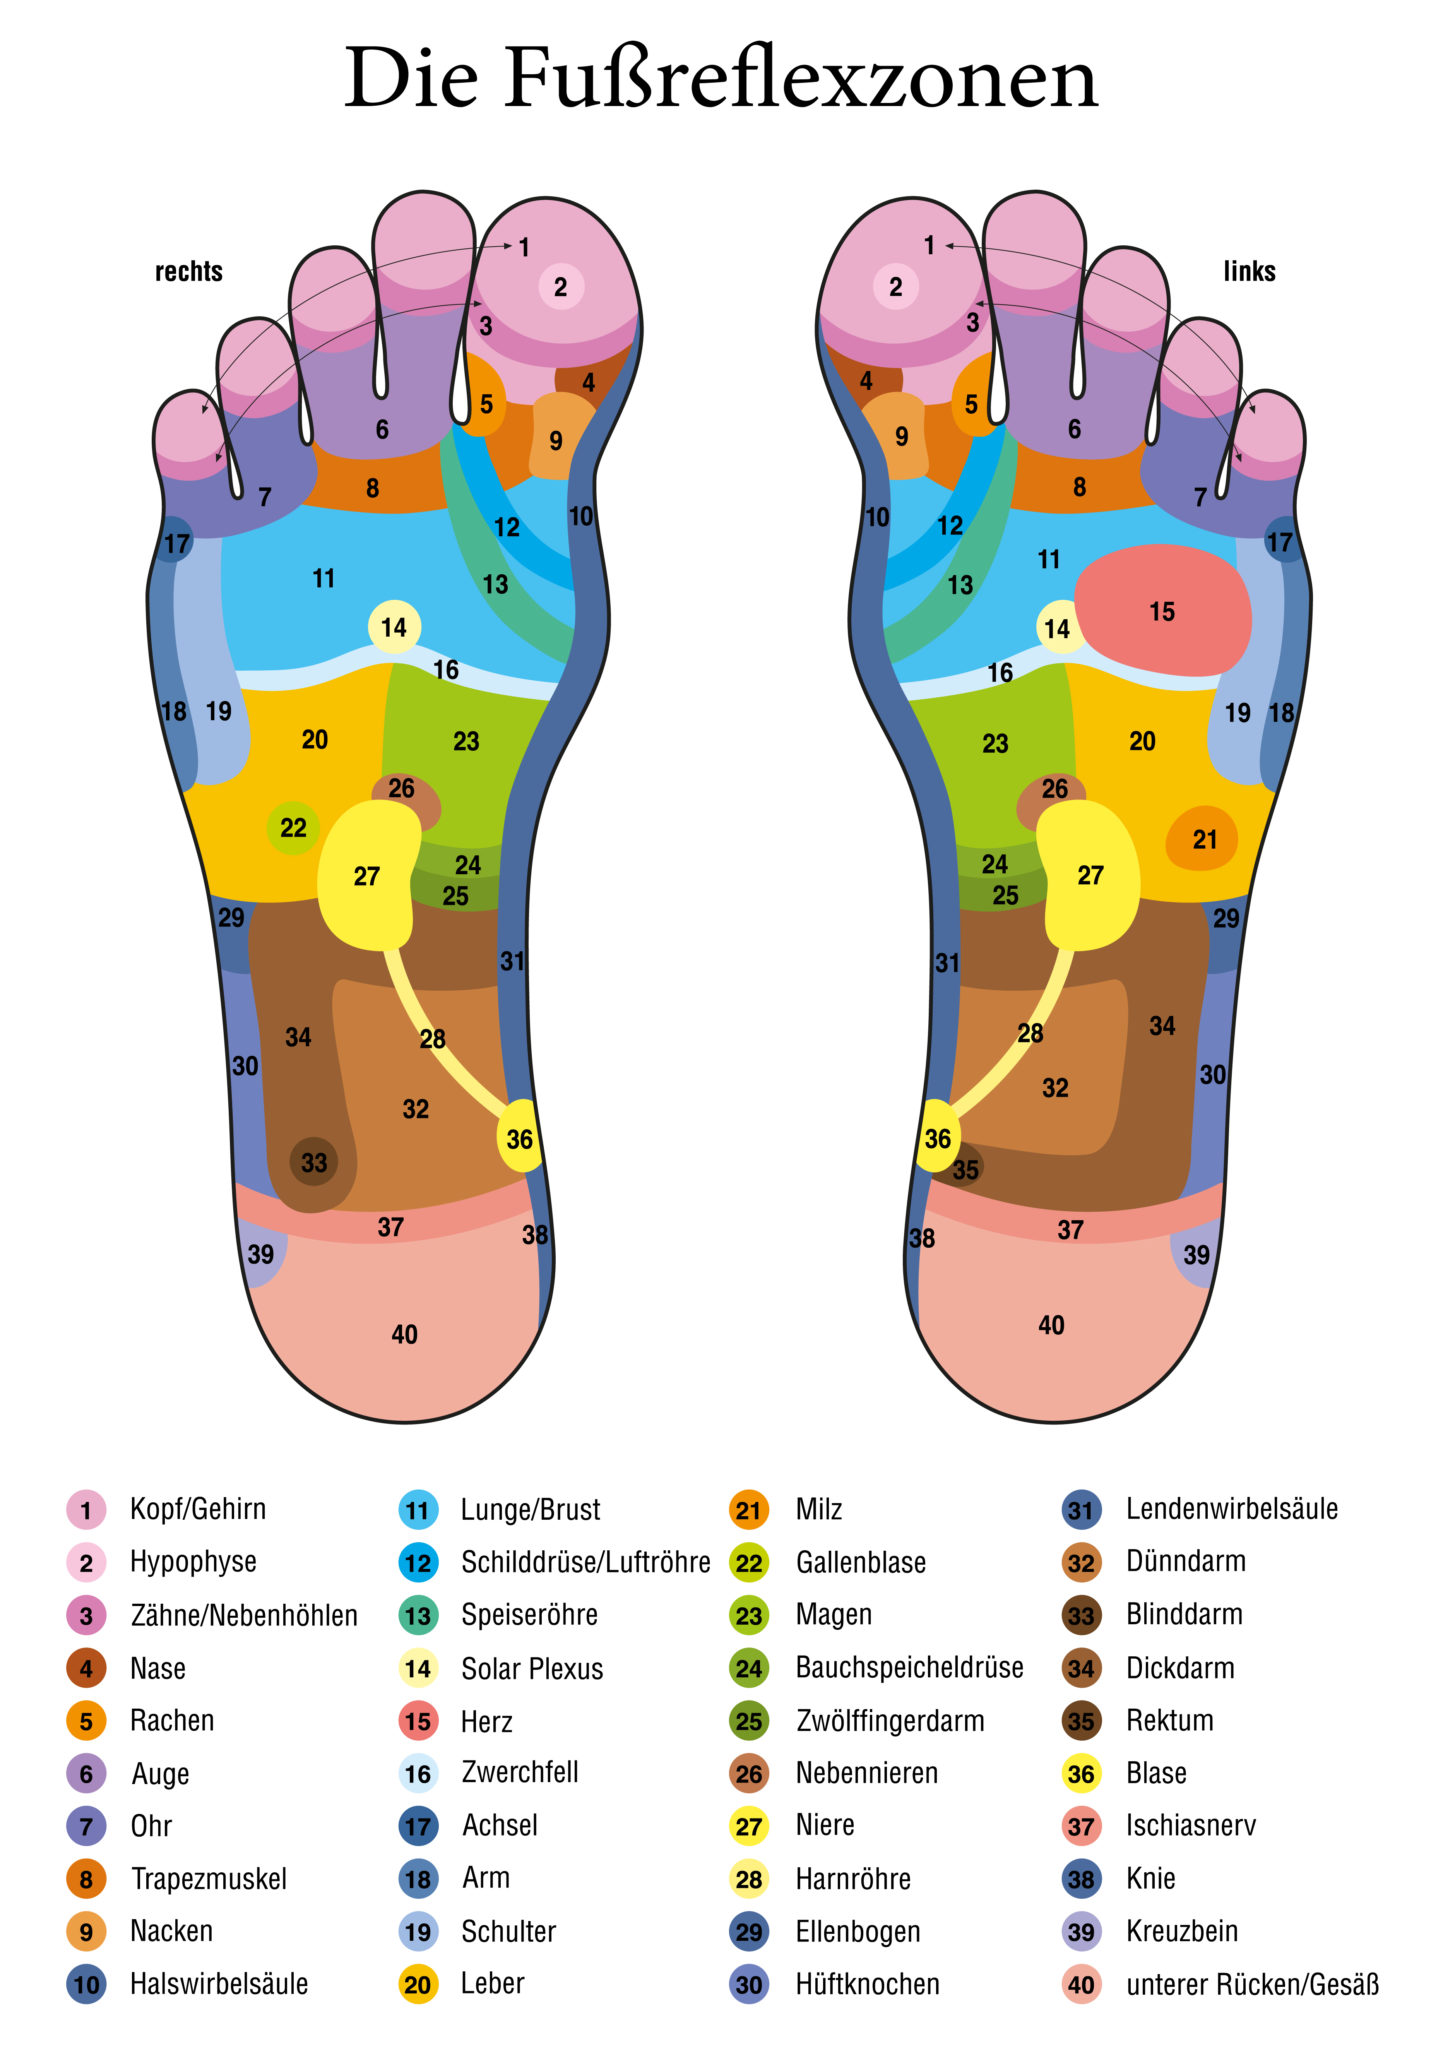

Fußreflexzonenmassage – Physio4nature.de

physio4nature.de